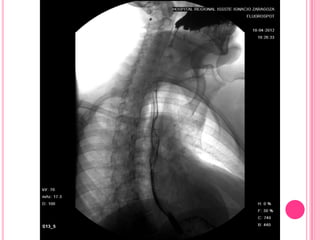

La SEGD muestra una estenosis concéntrica (flecha) en el tercio

esofágico medio en un paciente con esófago de Barret